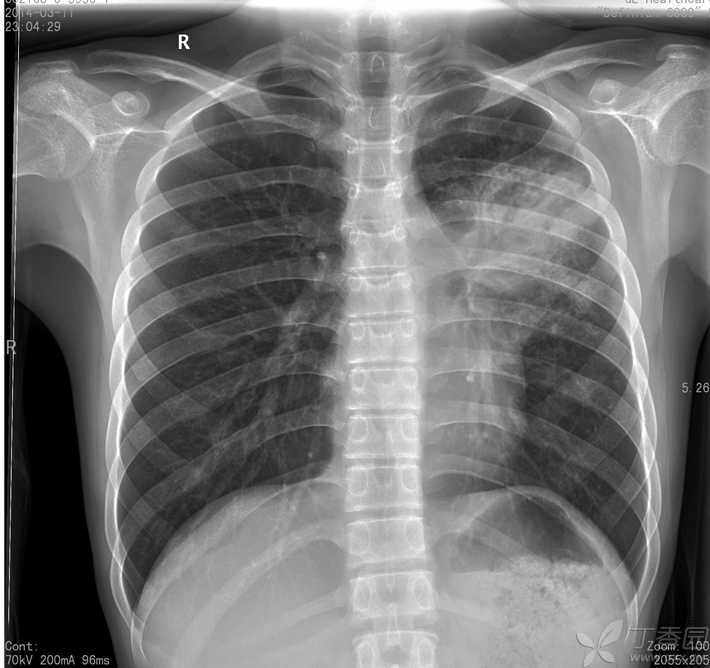

大叶性肺炎x线表现图

于2014-02-27拍胸片,诊断为大叶性肺炎; 在当地诊所抗炎治疗,10天左右

5.生化血凝无异常.血气正常.胸部ct:右肺上叶大叶性肺炎.